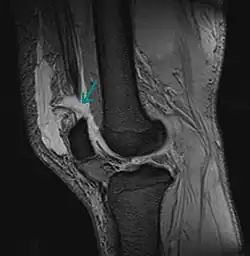

Riss der Quadrizepssehne oberhalb der Kniescheibe